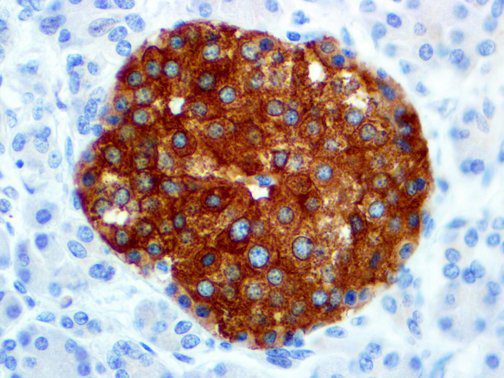

It is the ICU physician who is most likely to witness one of the deadliest manifestations of the abnormal immunological response, the cytokine storm syndrome (CSS). This response is also referred to by some as the cytokine release syndrome (CRS). CSS is characterized by continuous activation and expansion of macrophage and lymphocyte populations, which secrete large amounts of cytokines, causing the cytokine storm. This massive cytokine release is akin to hemophagocytic lymphohistiocytosis (HLH) disease, a syndrome characterized by initial unchecked and persistent activation of cytotoxic T lymphocytes and NK cells.

Clinical and laboratory manifestations of HLH include fever, enlarged liver and/or spleen, neurologic dysfunction, coagulopathy, liver dysfunction, cytopenias (i.e., low levels of erythrocytes, leukocytes, and/or platelets), hypertriglyceridemia, hyperferritinemia, hemophagocytosis, and eventually diminished NK cell activity as the immune system becomes progressively paralyzed. HLH can be familial (primary HLH) or secondary to another disease process (sHLH), such as rheumatic disease, in which it is referred to as macrophage activation syndrome (MAS, characterized by elevated ferritin).